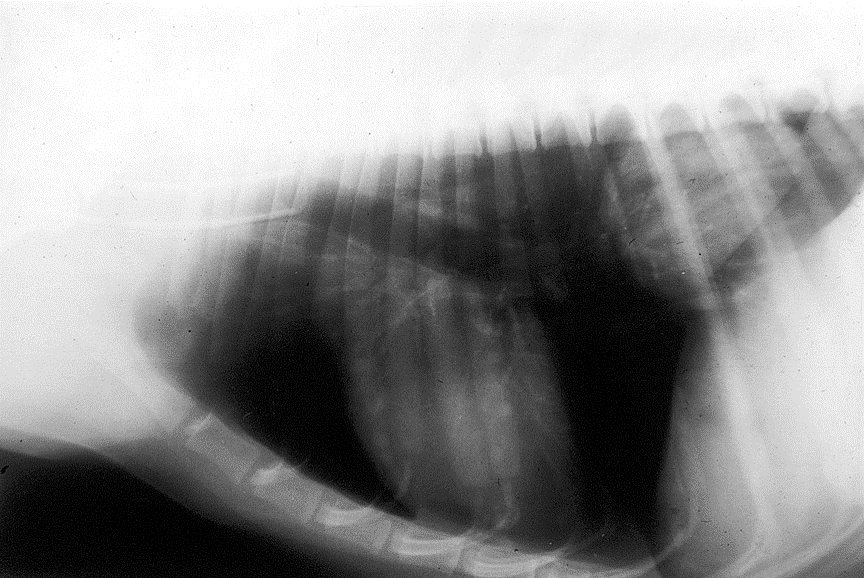

What can be seen in these images?

Dog that had thoracic surgery, has radio dense mass in throax which was displacing heart – chest opened up (middle pic) and heart put back in right place. Mass ended up being a large haemangiosarcoma – 6 months later, it reoccurred